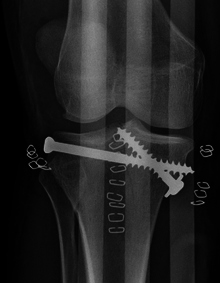

Treatment

Treatment is aimed at achieving a stable, aligned, mobile and painless joint and to minimize the risk of post-traumatic osteoarthritis. To achieve this operative or non-operative treatment plans are considered by physicians based on criteria such as patient characteristics, severity, risk of complications, fracture depression and displacement, degree of injury to ligaments and menisci, vascular and neurological compromise. For early management, traction should be performed early in ward. It can either be Skin Traction or Skeletal Traction. Depends on the body weight of patient and stability of the joint. Schantz pin insertion over the Calcaneum should be done from Medial to lateral side. Later when condition is stable. Definitive plan would be Buttress Plating and Lag Screw fixation.